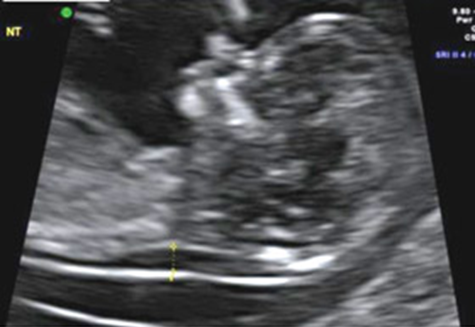

Gebelikte anne ve bebeğin sağlık durumunu değerlendirmek için yapılan tarama testlerinden biri de ikili testtir. Gebeliğin 11-14 haftaları arasında yapılan bu testte hem bebeğin ultrasonografik değerlendirmesi yapılmalı hem de anneden alınan kan örneğinde bir takım değerler bakılmalıdır. Bu test ile bebeğin kromozom sayılarında anormallik ile seyreden sık görülen Down Sendromu gibi genetik hastalıkların taraması yapılmaktadır. Güvenilirliği %75-85 oranındadır.

Annenin doğum tarihi, son adet tarihi, kilosu, sigara kullanımı, daha önce anomalili bebek öyküsü, akraba evliliği gibi bilgiler kaydedildikten sonra ultrasonografi ile bebek değerlendirilir. Bebeğin baş popo mesafesi ultrasonografi ile ölçülür, ardından ense kalınlığı ölçülür ve burun kemiği değerlendirilerek kaydedilir. Bebeğin tek mi ikiz mi olduğu belirtilmelidir. Ardından anneden alınan kan örneğinden HCG ve PAPP-A değerleri ölçülür. Tüm bilgiler istatistiksel olarak analiz edilerek kromozomal hastalıklar için risk analizi yapılır.